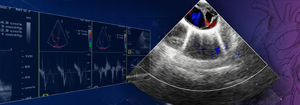

Warsztaty - Echokardiografia przezprzełykowa – aktualne wytyczne i praktyka